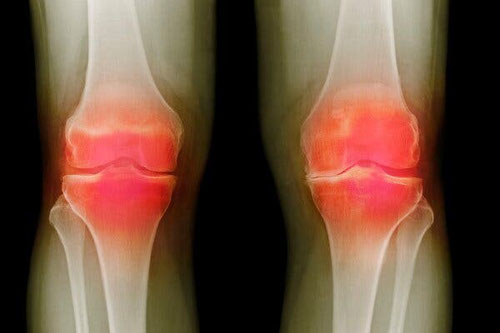

Photo - A colored X-ray of a 66-year-old patient with osteoarthritis. Credit...Dr. P. Marazzi/Science Source.